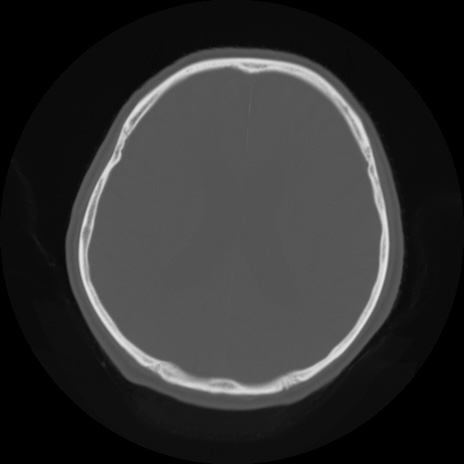

【頭部】症例5 CT(横断像)

症例5の画像所見と診断は?